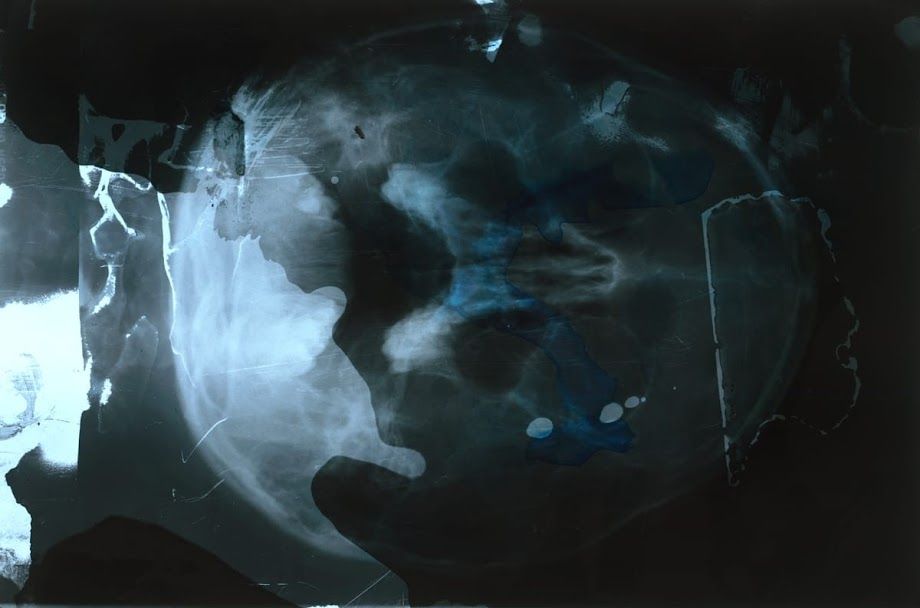

AU DELA DES CORPS PERDUS

Collection Une approche du corps — Série 2022

Pendant le COVID , aucun matériel pour travailler n'était disponible chez moi.

J'ai alors utilisé mes propres radiographies, des produits de ménage et des instruments du quotidien.

Je savais que le matériau de départ, les radiographies, allaient disparaitre, remplacées par des c.d.

Puis j'ai réussi à me procurer d'autres radiographies et mon dialogue avec la trace

et la disparition des corps a pu se rétablir.